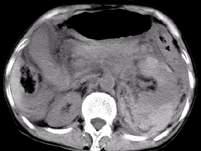

问题 男,37岁,左腰部疼痛伴血尿,有外伤史,CT检查如图所示,下列说法错误的是 ( )

选项 A、考虑为肾挫伤 B、考虑为肾包膜下出血 C、左侧肾实质增厚,其内密度不均,可见大片状不规则的高密度影 D、腹腔内可见较高密度的积液 E、左侧肾影增大模糊,肾轮廓消失

答案 B